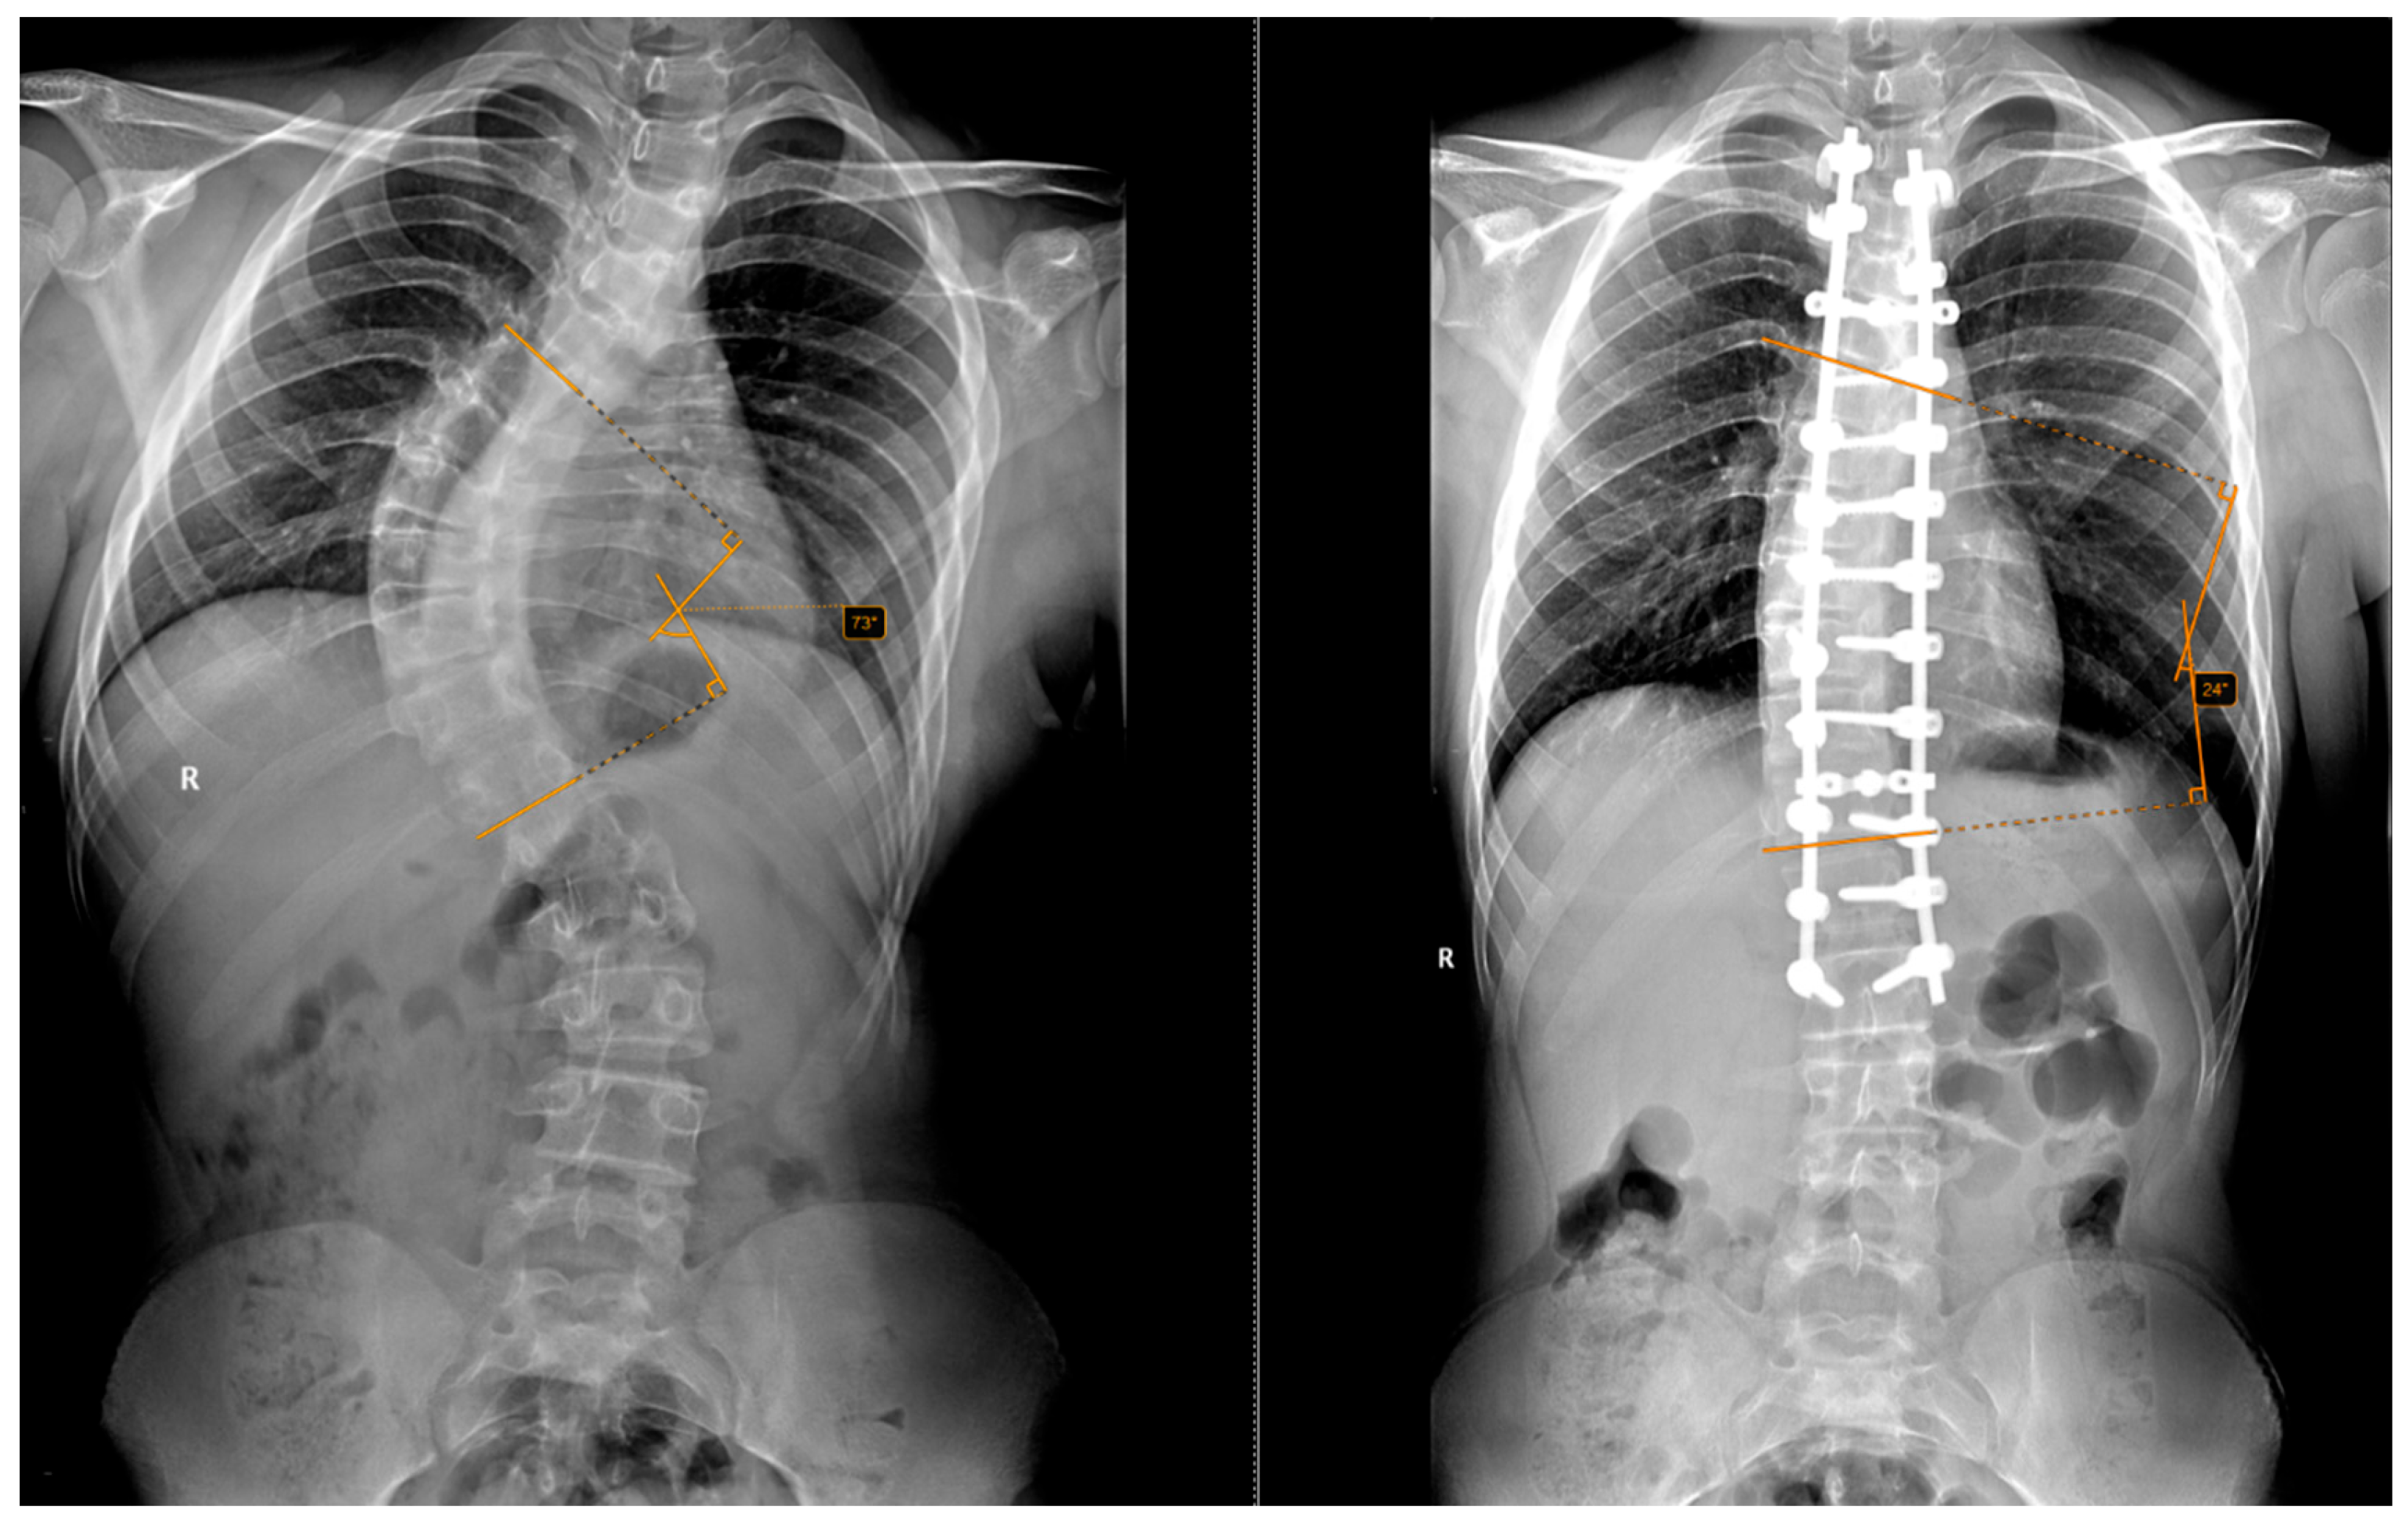

The inclusion criteria required a minimum follow-up of 12 months, complete clinical and radiological data, and informed consent to participate in the study. Standing anteroposterior and lateral full-spine radiographs were obtained preoperatively and postoperatively at 2 weeks, 1 month, 3 months, 6 months and annually thereafter. This is exemplified in Figure 2 and Figure 3.

Figure 2. Preoperative and postoperative radiographs of a 14-year-old patient who did not undergo halo-traction. The (left) image shows a preoperative Cobb angle of 73° for the main curve (T6–T12), while the (right) image shows the postoperative correction to 24°.